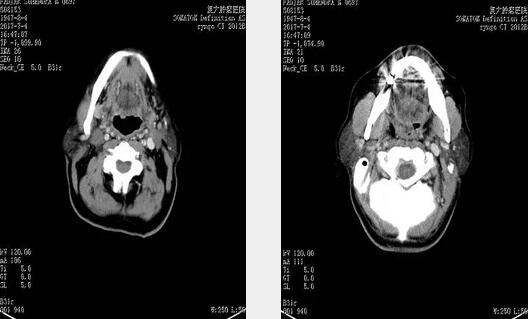

2017年7月4日颈部淋巴结清扫术后CT,原双侧颈部转移性病变,已消失。